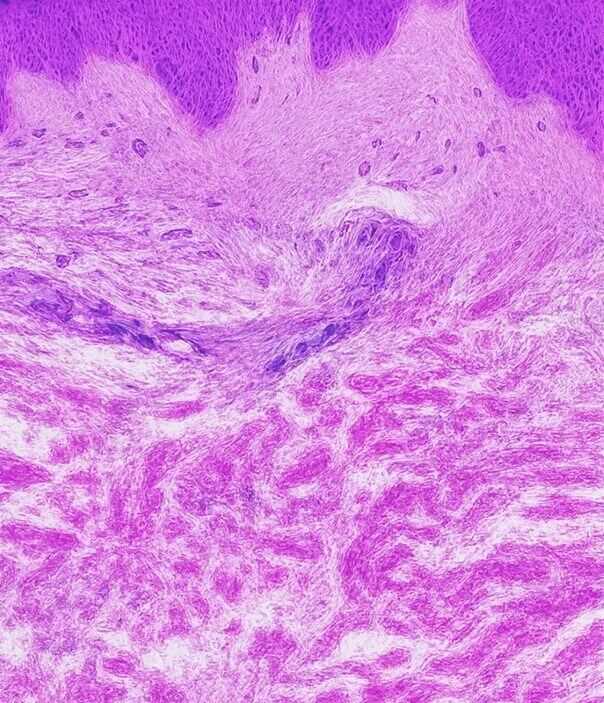

Dehnungsstreifen

Dehnungsstreifen

Normale Haut

Glatt und elastisch, wobei intakte Kollagen- und Elastinfasern für Festigkeit und Struktur sorgen.

Striae Rubrae

Glatt und elastisch, wobei intakte Kollagen- und Elastinfasern für Festigkeit und Struktur sorgen.

Striae Albae

Reife weiße Dehnungsstreifen, bei denen die Umstrukturierung des Kollagens zu einer Ausdünnung und einem Verlust der Pigmentierung führt.

So funktioniert es

- Fördert den Abbau von geschädigtem Kollagen

- Es induziert die Proliferation von Keratinozyten, die Wachstumsfaktoren freisetzen, um die Kollagenablagerung durch Fibroblasten und die Elastinablagerung zu fördern.

- Moduliert die Expression mehrerer Gene in der Haut (vaskulärer endothelialer Wachstumsfaktor, Fibroblasten-Wachstumsfaktor, epidermaler Wachstumsfaktor, Kollagen Typ I und III), die die Umgestaltung der extrazellulären Matrix fördern.